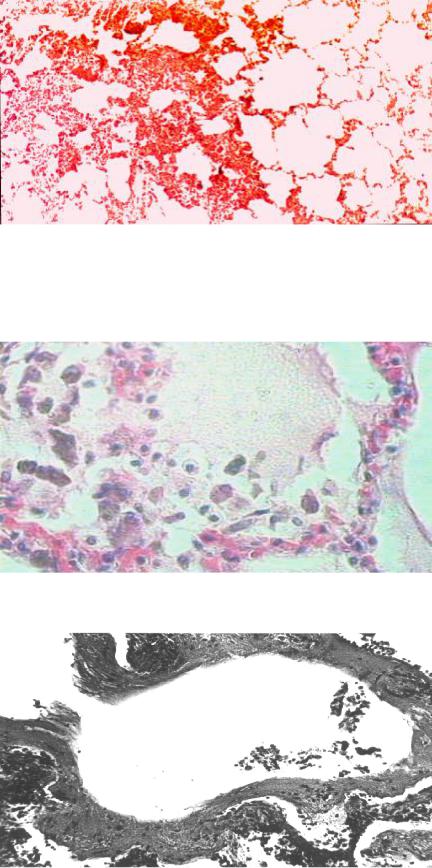

В первой фазе (альтеративной) морфологические изменения характеризу- ются преимущественно вентиляционно-перфузионными нарушениями в виде дис- телектазов чередующихся мелких участков ателектазов и эмфиземы (рис. 44).

Рис. 44. Микропрепарат легкого в I фазе ОДН:

чередующиеся мелкие участки ателектазов и эмфиземы дистелек- тазы (окраска гематок- силином и эозином, × 100), рисунок И. В. Ти-

мофеева

Вторая фаза (экссудативная) морфологически проявляется диффузным альвеолитом, характеризующимся наличием в просветах альвеол отечной жид- кости (мембраногенным отеком), эритроцитов, десквамированных альвеолоци- тов и значительного количества макрофагов (рис. 45).

Рис. 45. Микропрепарат легкого во II фазе ОДН: диффузный альвеолит

в просветах альвеол отечная жидкость, эрит- роциты, десквамирован- ные альвеолоциты, аль-

веолярные макрофаги (окраска гематоксили- ном и эозином, × 500), рисунок М. В. Рогачева

В альвеолах можно обнаружить пристеночно расположенные белковые мас- сы, дающие селективные окраски на фибрин — «гиалиновые мембраны» (рис. 46).